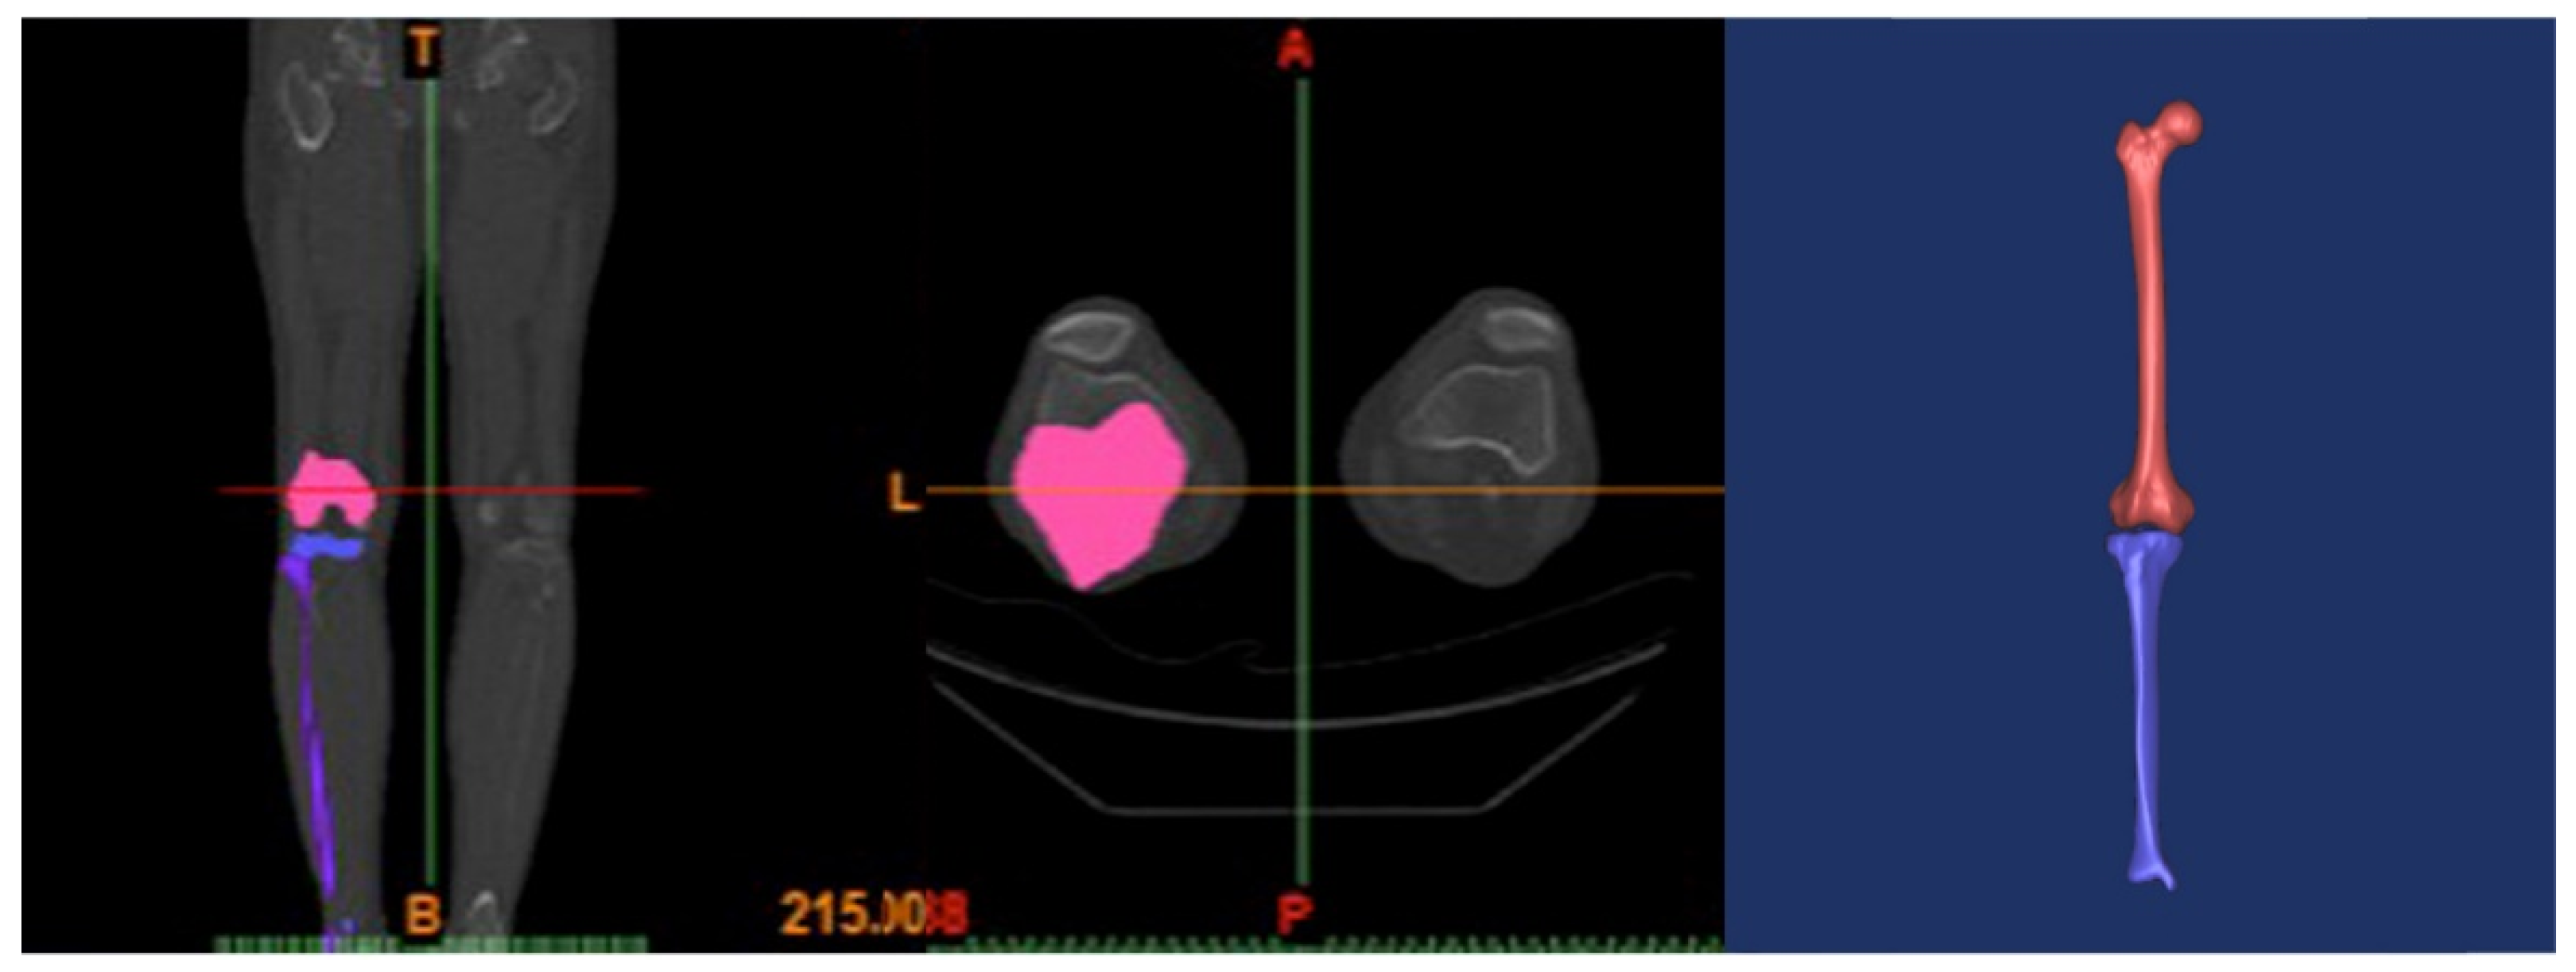

2.1. Intact Model